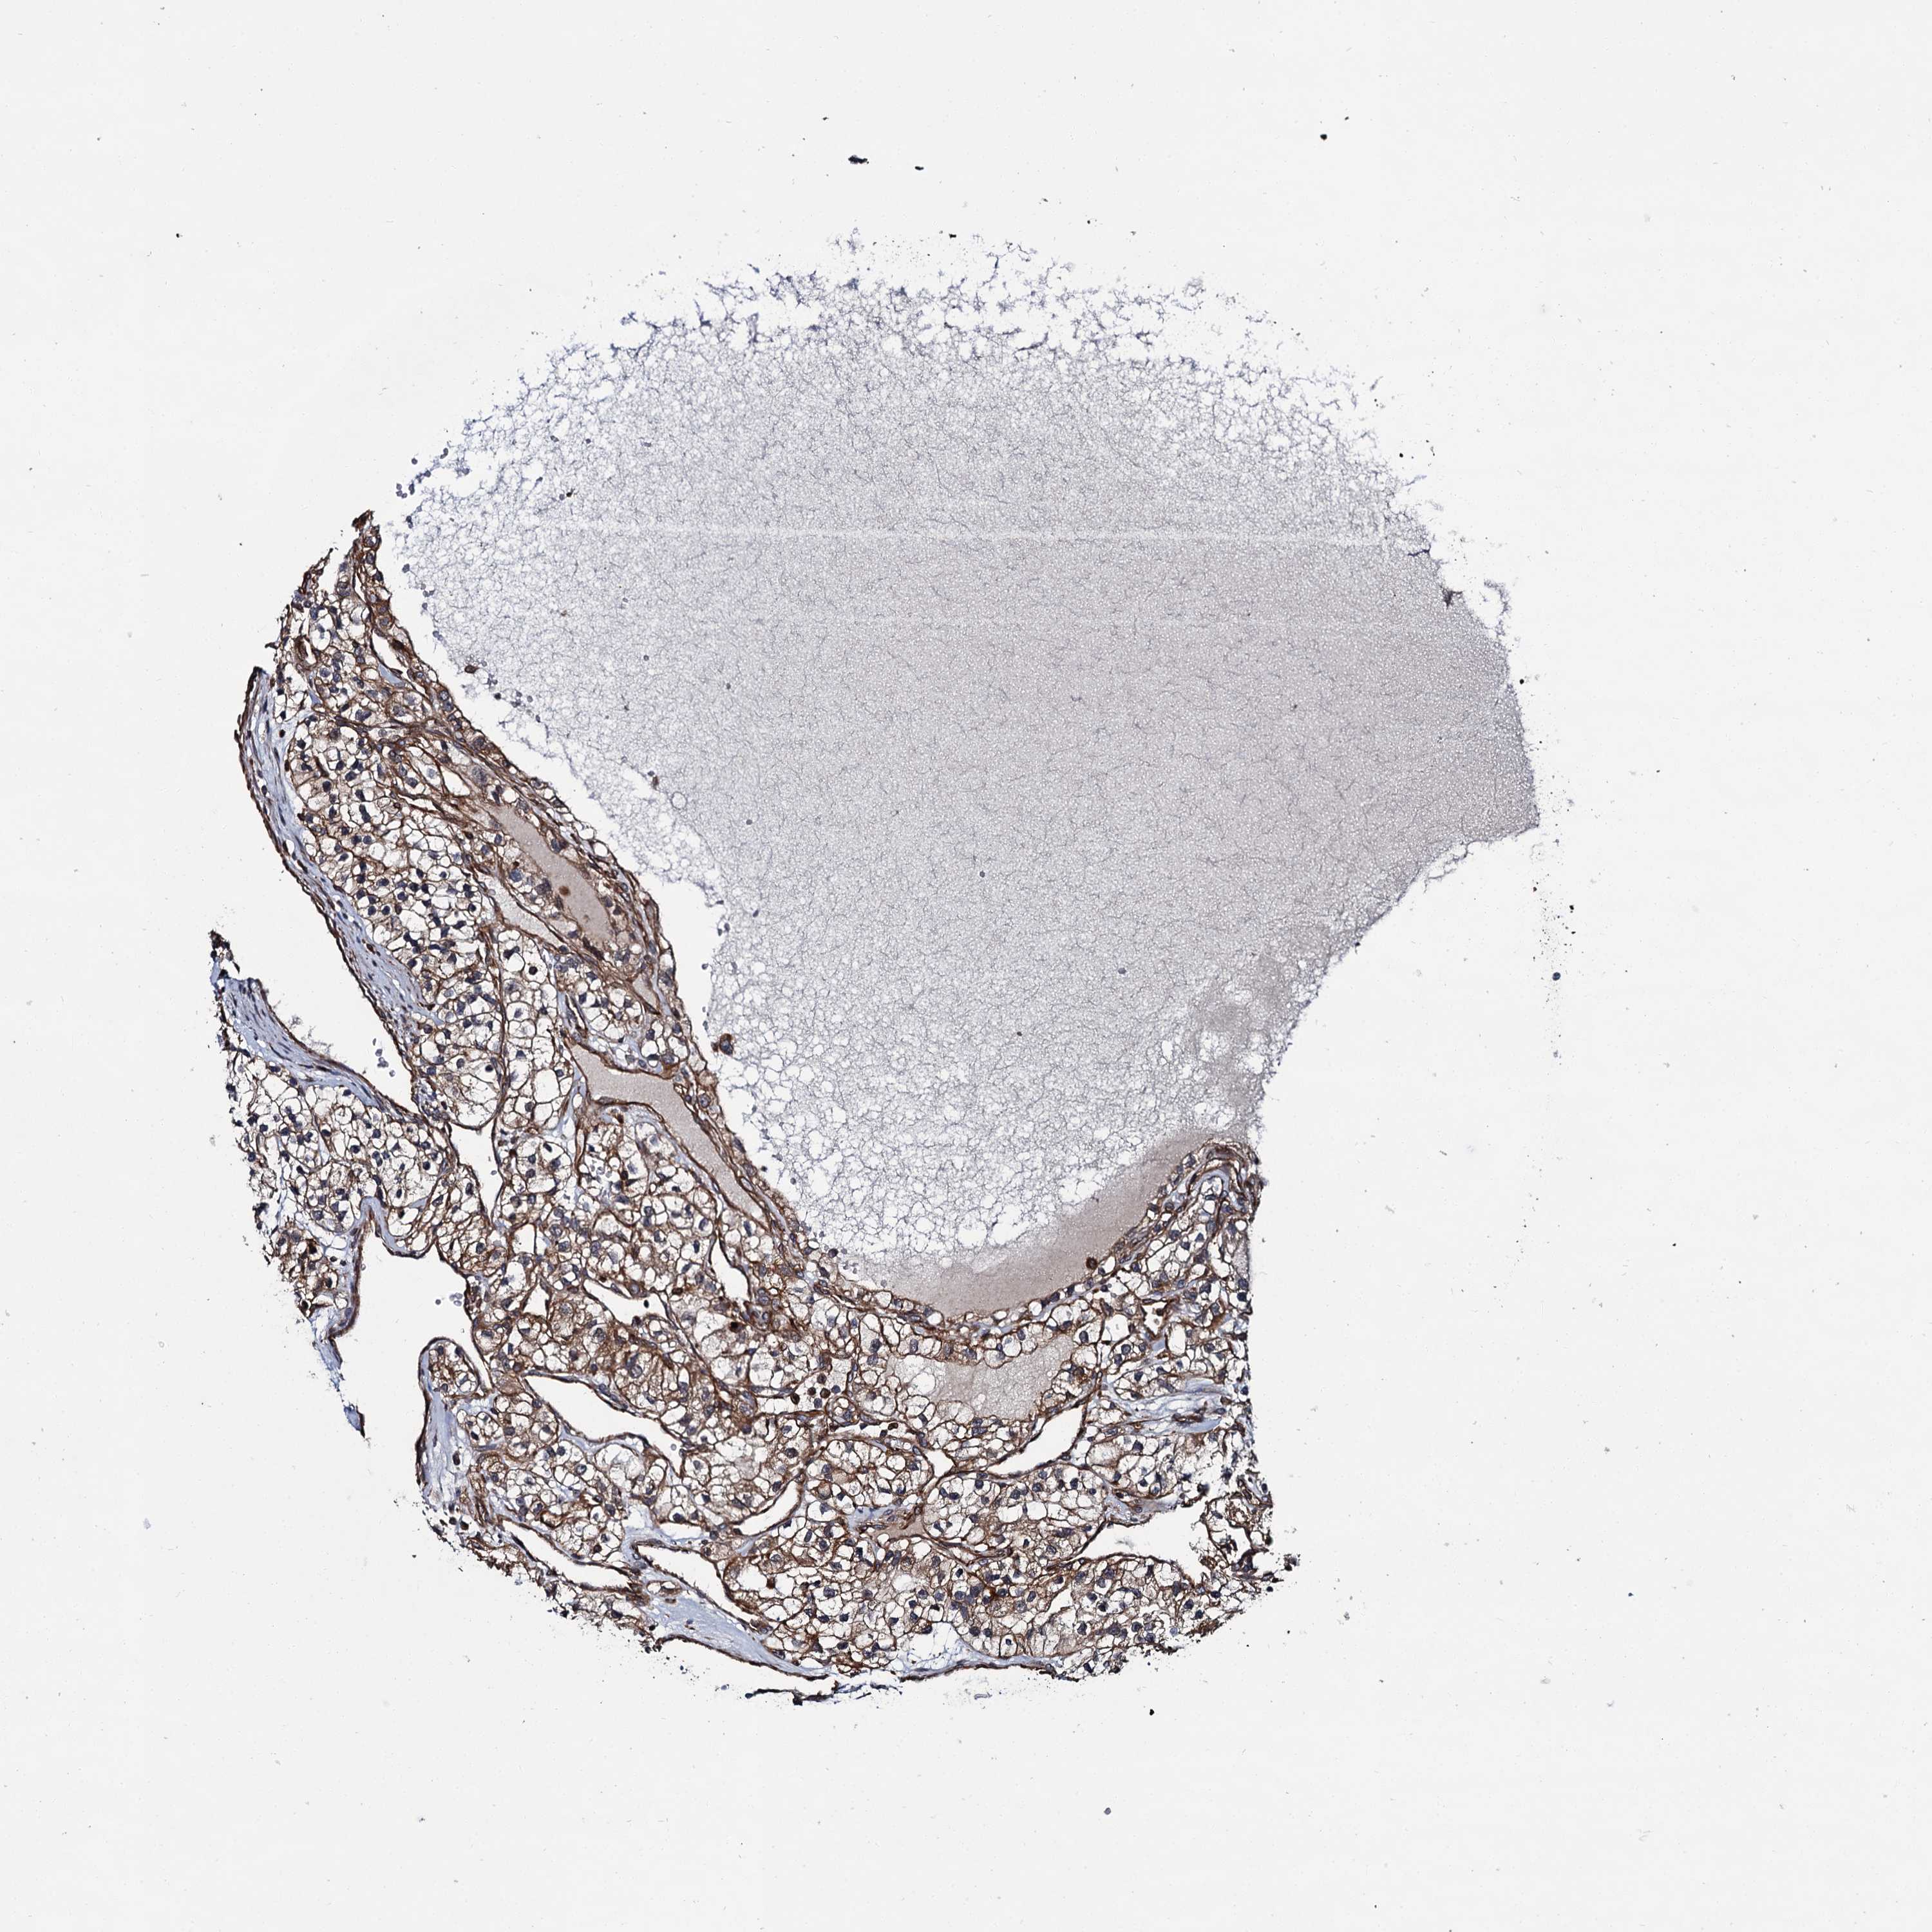

KIDNEY RENAL CLEAR CELL CARCINOMA (VALIDATION) - Interactive survival scatter ploti

The Survival Scatter plot shows the clinical status (i.e. dead or alive) for all individuals in the patient cohort, based on the same data that underlies the corresponding Kaplan-Meier plots. Patients that are alive at last time for follow-up are shown in blue and patients who have died during the study are shown in red.

The x-axis shows the expression levels (FPKM) of the investigated gene in the tumor tissue at the time of diagnosis. The y-axis shows the follow-up time after diagnosis (years). Both axes are complimented with kernel density curves demonstrating the data density over the axes. The top density plot shows the expression levels (FPKM) distribution among dead (red) and alive patients (blue). The right density plot shows the data density of the survived years of dead patients with high and low expression levels respectively, stratified using the cutoff indicated by the vertical dashed line through the Survival Scatter plot. This cutoff is automatically defined based on the FPKM cutoff that minimizes the p-score. The cutoff can be changed by dragging the vertical line or by entering a cutoff value in the square labeled "Current cut-off".

Under the Survival Scatter plot the p-score landscape (black curve; left axis) is shown together with dead median separation (red curve; right axis). Dead median separation is the difference in median mRNA expression between patients who have died with high and low expression, respectively. It is calculated as follows: median FPKM expression of dead patients with high expression - median FPKM expression of dead patients with low expression. This is intended to aid the user in visually exploring custom cutoffs and the associated p-scores and dead median separation.

Individual patient data is displayed and can be filtered by clicking on one or more of the category buttons on the top of the page. Categories describing expression level and patient information include: high, low, alive, dead, female, male and tumor stages. The scale of the x-axis can be toggled between linear and log-scale by clicking on the "x log" button. Mouse-over function shows TCGA ID, patient information and mRNA expression (FPKM) for each patient.

& Survival analysisi

Kaplan-Meier plots summarize results from analysis of correlation between mRNA expression level and patient survival. Patients were divided based on level of expression into one of the two groups "low" (under cut off) or "high" (over cut off). X-axis shows time for survival (years) and y-axis shows the probability of survival, where 1.0 corresponds to 100 percent.

ZFYVE19 is validated prognostic, high expression is favorable in Kidney Renal Clear Cell Carcinoma (validation)

Best expression cut offi

Based on the FPKM value of each gene, patients were classified into two groups and association between prognosis (survival) and gene expression (FPKM) was examined. The best expression cut-off refers the FPKM value that yields maximal difference with regard to survival between the two groups at the lowest log-rank P-value. Best expression cut-off was selected based on survival analysis .

When clicking on this number, the vertical dashed line indicating cut-off, the interactive survival plot, and the Kaplan-Meier curve will be adjusted to show results based on the best expression cut-off.

: 11.38

TCGA RNA samplesi

RNA-seq data is reported as average FPKM (number Fragments Per Kilobase of exon per Million reads), generated by the The Cancer Genome Atlas (TCGA) .

Normal distribution across the dataset is visualized with box plots, shown as median and 25th and 75th percentiles. Points are displayed as outliers if they are above or below 1.5 times the interquartile range. FPKM values of the individual samples are presented next to the box plot.

Average pTPM 12.9

Number of samples 100